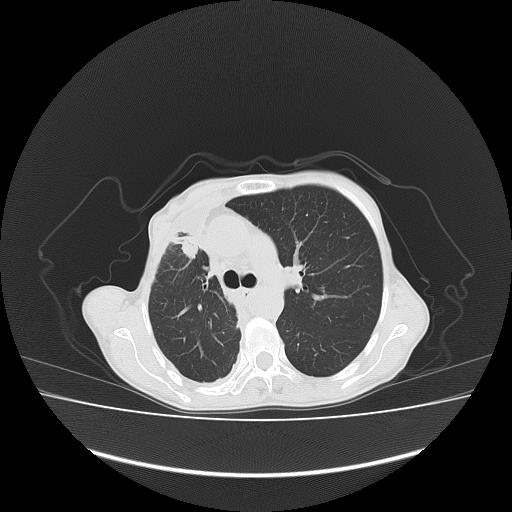

标题: CT16930:女 59 胸痛6个月 胸水脱落细胞学见瘤细胞 [打印本页]

可见多发肺内病灶,且胸膜病灶较多有圆球状而非丘状,多考虑胸膜转移瘤伴胸腔积液,右侧胸廓缩小固定,且部分病灶呈丘状,尚不除外恶性胸膜间皮瘤伴肺内转移

右侧胸膜增厚,局部呈结节状增厚,右侧胸腔少量积液。双肺未见确切肿块影。纵隔未见淋巴结肿大。气管、支气管通畅。考虑右侧胸膜间皮瘤(恶性?)可能性大。不除外癌性胸膜炎。

恶性胸膜间皮瘤伴肺内转移可能性大;或胸膜、肺内均为转移瘤,左肺下叶亦见多发小结节影。

右侧胸廓塌陷,右侧胸膜广泛增厚并见多发胸膜结节,右侧少量胸腔积液并包裹。

右侧广泛胸膜增厚,局部呈结节状增厚,右侧胸腔少量积液。双肺未见确切肿块影。纵隔未见淋巴结肿大。气管、支气管通畅。考虑右侧胸膜间皮瘤(恶性?)可能性大。支持!

右胸腔结节均考虑来自胸膜(部分来源于叶裂),考虑胸膜间皮瘤或转移瘤.